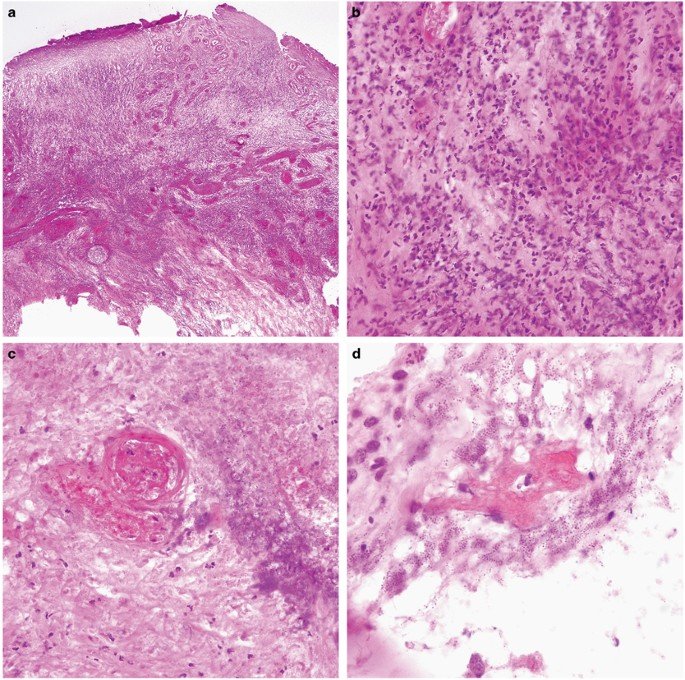

Цей клінічний випадок описує рідкісне, але вкрай тяжке ускладнення після косметичної процедури — некротизуючу інфекцію м’яких тканин (NSTI) та множинні перфорації кишечника після ліпосакції.

Некротизуючі інфекції м’яких тканин та множинні перфорації кишечника після ліпосакції є рідкісними, але надзвичайно тяжкими ускладненнями. Цей випадок підкреслює критичні виклики, пов’язані з такими інфекціями, особливо при наявності великих ран та системних ускладнень, включаючи септичний шок та гостру ниркову недостатність.

SilverStream ефективно зменшив бактеріальну та грибкову біоплівку, яка є поширеною перешкодою для загоєння масивних інфікованих ран.

Унікальна формула SilverStream (іони срібла в гіпертонічному розчині) діяла вибірково на біоплівку та патогени, не пошкоджуючи здорові тканини, навіть на такій великій рановій поверхні.

Антимікробна дія SilverStream сприяла зменшенню інфекційного навантаження, що було критично важливим для контролю септичного стану та стимуляції грануляції.